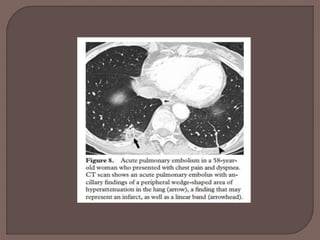

 Peripheral wedge-shaped areas of

hyperattenuation that may represent infarcts,

along with linear bands, have been

demonstrated to be statistically significant

ancillary findings associated with acute

pulmonary embolism.

 However, these radiologic features are not

specific for pulmonary embolism.